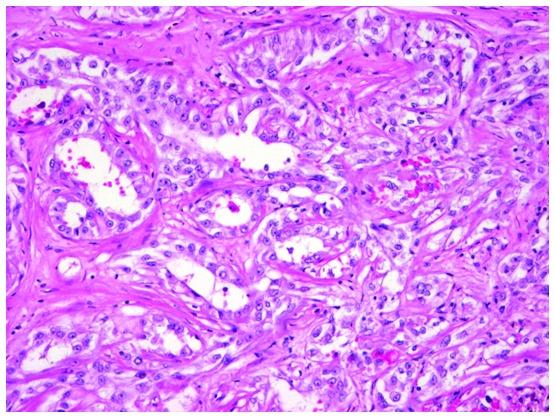

Mucinous tubular and spindle cell carcinoma (MTSCC) is a relatively rare renal epithelial neoplasm. Although MTSCC is considered to be a low-grade and indolent neoplasm, aggressive cases have been recently reported. The present study discussed two additional cases of high-grade MTSCC causing multiple distant metastases with a fatal course. In case 1, a 71-year-old patient presented with hematuria and pyuria. Computed tomography (CT) scan of the right kidney revealed a mass lesion, for which partial nephrectomy was performed. However, a follow-up CT imaging revealed distant metastases in the liver, the paraaortic lymph nodes and the bone. Despite molecular targeted therapy and irradiation, the patient succumbed due to tumor progression. In case 2, a 64-year-old patient presented with an incidentally identified mass lesion in the right kidney. A laparoscopic nephrectomy was performed, and a follow-up CT imaging revealed metastases in the skin and lungs. The cytology of pleural effusion revealed pleuritis carcinomatosa. Histologically, both cases were diagnosed as mucin-poor MTSCC with high-grade transformation, which comprised uniform tumor cells primarily forming slender tubules. The tumors contained low- and high-grade regions. In addition, venous invasion and necrosis were observed. The tumor cells also demonstrated increased Ki-67 labeling indices and cellular tumor antigen p53 (p53) nuclear accumulation. High-grade transformation, large tumor size, necrosis, venous invasion, high Ki-67 labeling index and p53 nuclear accumulation are generally predictive findings for aggressive behavior of malignant tumors. In the current report, it was emphasized that MTSCC possesses a wide spectrum of clinicopathological features. Thus, careful postoperative investigation is required for MTSCC with high-grade elements due to its aggressive nature.

黏液性小管状和梭形细胞癌(MTSCC)是一种相对罕见的肾上皮性肿瘤。尽管MTSCC被认为是一种低级别、惰性肿瘤,但最近有侵袭性病例的报道。本研究讨论了另外两例高级别MTSCC导致多发远处转移并呈致命病程的病例。病例1,一名71岁患者出现血尿和脓尿。右肾计算机断层扫描(CT)显示有一个肿块病变,为此进行了部分肾切除术。然而,后续CT成像显示肝脏、腹主动脉旁淋巴结和骨骼有远处转移。尽管进行了分子靶向治疗和放疗,患者仍因肿瘤进展而死亡。病例2,一名64岁患者偶然发现右肾有一个肿块病变。进行了腹腔镜肾切除术,后续CT成像显示皮肤和肺部有转移。胸腔积液细胞学检查显示为癌性胸膜炎。组织学上,两例均诊断为伴有高级别转化的黏液缺乏型MTSCC,由主要形成细长小管的均匀肿瘤细胞组成。肿瘤包含低级别和高级别区域。此外,观察到静脉侵犯和坏死。肿瘤细胞还显示Ki-67标记指数增加和细胞肿瘤抗原p53(p53)核积聚。高级别转化、肿瘤体积大、坏死、静脉侵犯、高Ki-67标记指数和p53核积聚通常是恶性肿瘤侵袭行为的预测性表现。在本报告中,强调了MTSCC具有广泛的临床病理特征。因此,由于其侵袭性,对于伴有高级别成分的MTSCC,术后需要仔细检查。